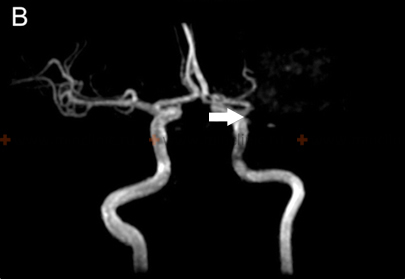

| იშემიური ინსულტი / TIA (წინა მიმოქცევა) | უეცრად დაწყებული კეროვანი დეფიციტი (ჰემიპარეზი სახე/მკლავი > ფეხი, ჰემისენსორული დაკარგვა, აფაზია, უგულებელყოფა, ფეხის > მკლავის სისუსტე [ACA]). Amaurosis fugax შესაძლებელია (ICA). | თავის კტ გამორიცხავს სისხლჩაქცევას. მრტ (DWI) ადასტურებს იშემიას. საძილე/ცერებრალური სისხლძარღვოვანი ვიზუალიზაცია (ულტრაბგერა, CTA, MRA, DSA) ავლენს ოკლუზიას/სტენოზს/წყაროს (ICA, ემბოლია). |